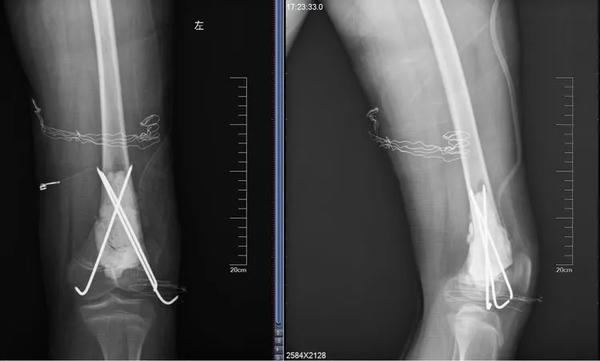

12歲的男孩兒浩浩,在學校上體育課,扭傷后突發(fā)右側(cè)大腿劇烈疼痛,不能活動,被家人緊急送到醫(yī)院,當?shù)蒯t(yī)院拍片后提示右股骨中下段斜行骨折。隨后,醫(yī)院按照一般骨折處理。

當?shù)蒯t(yī)生將病理組織送河南省腫瘤醫(yī)院病理會診,提示為骨肉瘤。消息猶如晴天霹靂,但更讓兩個孩子的父母痛苦的是,“由于按一般骨折做了手術(shù)、打了鋼板和鋼釘,破壞了腫瘤外面原本相對完整的包膜,這個自然屏障一旦被破壞,腫瘤細胞就會‘污染’周圍組織,以后想再切干凈就更困難了。”河南省腫瘤醫(yī)院骨與軟組織科主任、主任醫(yī)師姚偉濤表示。

身體異常:排除感冒、發(fā)燒引起的,患者出現(xiàn)持續(xù)發(fā)熱,并伴有體重下降,活動能力下降,且有難以解釋的持續(xù)性疼痛。骨折:腫瘤持續(xù)“破壞蠶食”骨質(zhì),最后就像浩浩和晨晨一樣,輕微的外力下就會發(fā)生一處甚至多處骨折。揪出骨肉瘤 核磁是關(guān)鍵那怎么才能確診骨肉瘤呢?檢查骨肉瘤首先要拍X片,其次是磁共振,最終要依靠活組織檢查來確診。一定不能忽視磁共振檢查。王鑫提醒道:骨肉瘤就像一個表面看起來很小的水坑,實際上坑里的水已經(jīng)向周圍浸潤了很大一片。在X光片上僅能看到很小的一個病灶,而在磁共振上,可以判斷腫瘤的實際大小和確切范圍,減少誤診漏診。就像浩浩、晨晨這樣,以為只是骨折,拍了片子,即使看出有一些異常,也可能沒在意,這樣打鋼板、鋼釘,弄破了瘤子后期治療就不好進行了。磁共振不僅對確診有幫助,而且對治療也有指導(dǎo)作用。“手術(shù)時要在腫瘤周圍正常組織內(nèi)切除腫瘤,保證腫瘤的邊界干凈,才能提高治愈效果。”王鑫解釋說。

最終,王鑫醫(yī)師組為浩浩、晨晨兩位小朋友選擇了新輔助化療,待疼痛癥狀緩解后,手術(shù)取出鋼板、鋼釘,并通過擴大切除手術(shù),完整切除長瘤子部分的股骨,并進行體外滅活,搭配腫瘤型組配人工膝關(guān)節(jié)置換,達到了既完整切除腫瘤,又保全了孩子肢體功能的目的。做到這些讓孩子遠離骨肉瘤骨肉瘤的致病原因目前并不明確,常認為是多種因素綜合導(dǎo)致,比如放射性輻射、接觸化學物質(zhì)、基因突變等。首先,家長對于孩子出現(xiàn)身體異常,一定要引起重視,發(fā)現(xiàn)子女在不明確病因的情況下出現(xiàn)了骨頭疼痛、關(guān)節(jié)腫痛,請及時前往醫(yī)院查明病因;家長要多鼓勵孩子外出進行戶外運動,不要接觸過多放射性輻射;另外,戶外運動時,也要注意關(guān)節(jié)處的保護,提醒孩子注意運動秩序和方式,避免造成骨骼損傷及軟組織拉傷。王鑫提醒,如果出現(xiàn)問題,懷疑骨腫瘤性疾病,尤其是合并病理性骨折,家長一定要帶孩子到專業(yè)的骨腫瘤科就診,必要時行磁共振檢查,仔細甄別骨折原因!